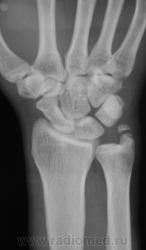

Перелом шиловидного отростка локтевой кости? Или я чего-то еще не замечаю?

Без костно-травматических изменений. В данном случае либо неслияние ядра окостенения ш. отростка, либо б-нь Мюллера, тут уж клиницист должен д/д проводить.

Поддержу не слияние, клиника травмы значит в пользу Мюллера данные вряд ли будут.

Без видимых костных повреждений; вариант окостенения шиловидного отростка локтевой кости.

Пациент предъявляет жалобы на боли и прочее необходимое... Рассказывает о наличии бывшей накануне травмы, со слов друга, сопровождавшего его, пациент "конкретный пацан" и "своего не упустит". Была сделана "цифра" и соответственно на сиаре увеличили изображение. Все ровненько, все прекрасно. Протокольно  написали "норму", пациент был недоволен, сначала угрожал, но потом спор прекратился. Он прекрасно знает о своём "состоянии" и время от времени этим пользуется, правда посещая разных врачей и вырывая записи из своей амбулаторной карты.

Вот такие дела...